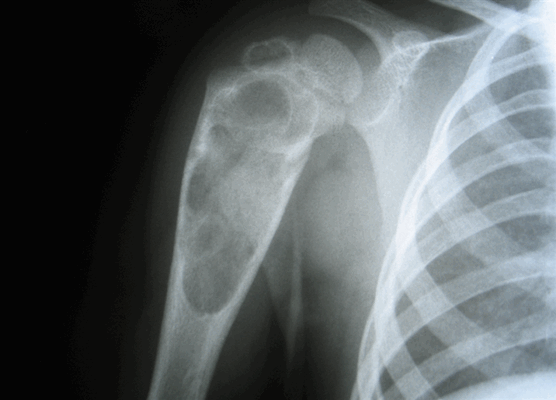

Чаще всего патология встречается у детей и подростков. Практически 75% больных с таким диагнозом моложе 20 лет. Эозинофильная гранулема может образовываться в любой кости скелета, но замечено, что у молодых людей она преимущественно формируется в костях черепа (70%), а также в эпифизах (головках) и метафизах (шейках) длинных трубчатых костей (бедренной, большеберцовой, плечевой).

У тех же, кто старше 20 лет, образование чаще обнаруживается в ребрах и нижней челюсти. Реже страдают кости таза, позвоночника и лопатки. При множественном поражении опухолеподобные образования в основном выявляются в бедренной кости и костях черепа.

Наиболее часто поражаются кости черепа, бедренные кости, реже — кости таза, ребра, позвонки. Известны также случаи появления патологических очагов в тимусе, коже, мочевом пузыре, паращитовидных железах, гипоталамусе, легких и желудочно-кишечном тракте.

- Рентгенография костей. При рентгенологическом исследовании определяются единичные или множественные опухолевидные образования, участки деструкции, которые могут располагаться как в трубчатых, так и в плоских костях. При подозрении на эозинофильную гранулему обязательно проводят рентгенографию челюстей.